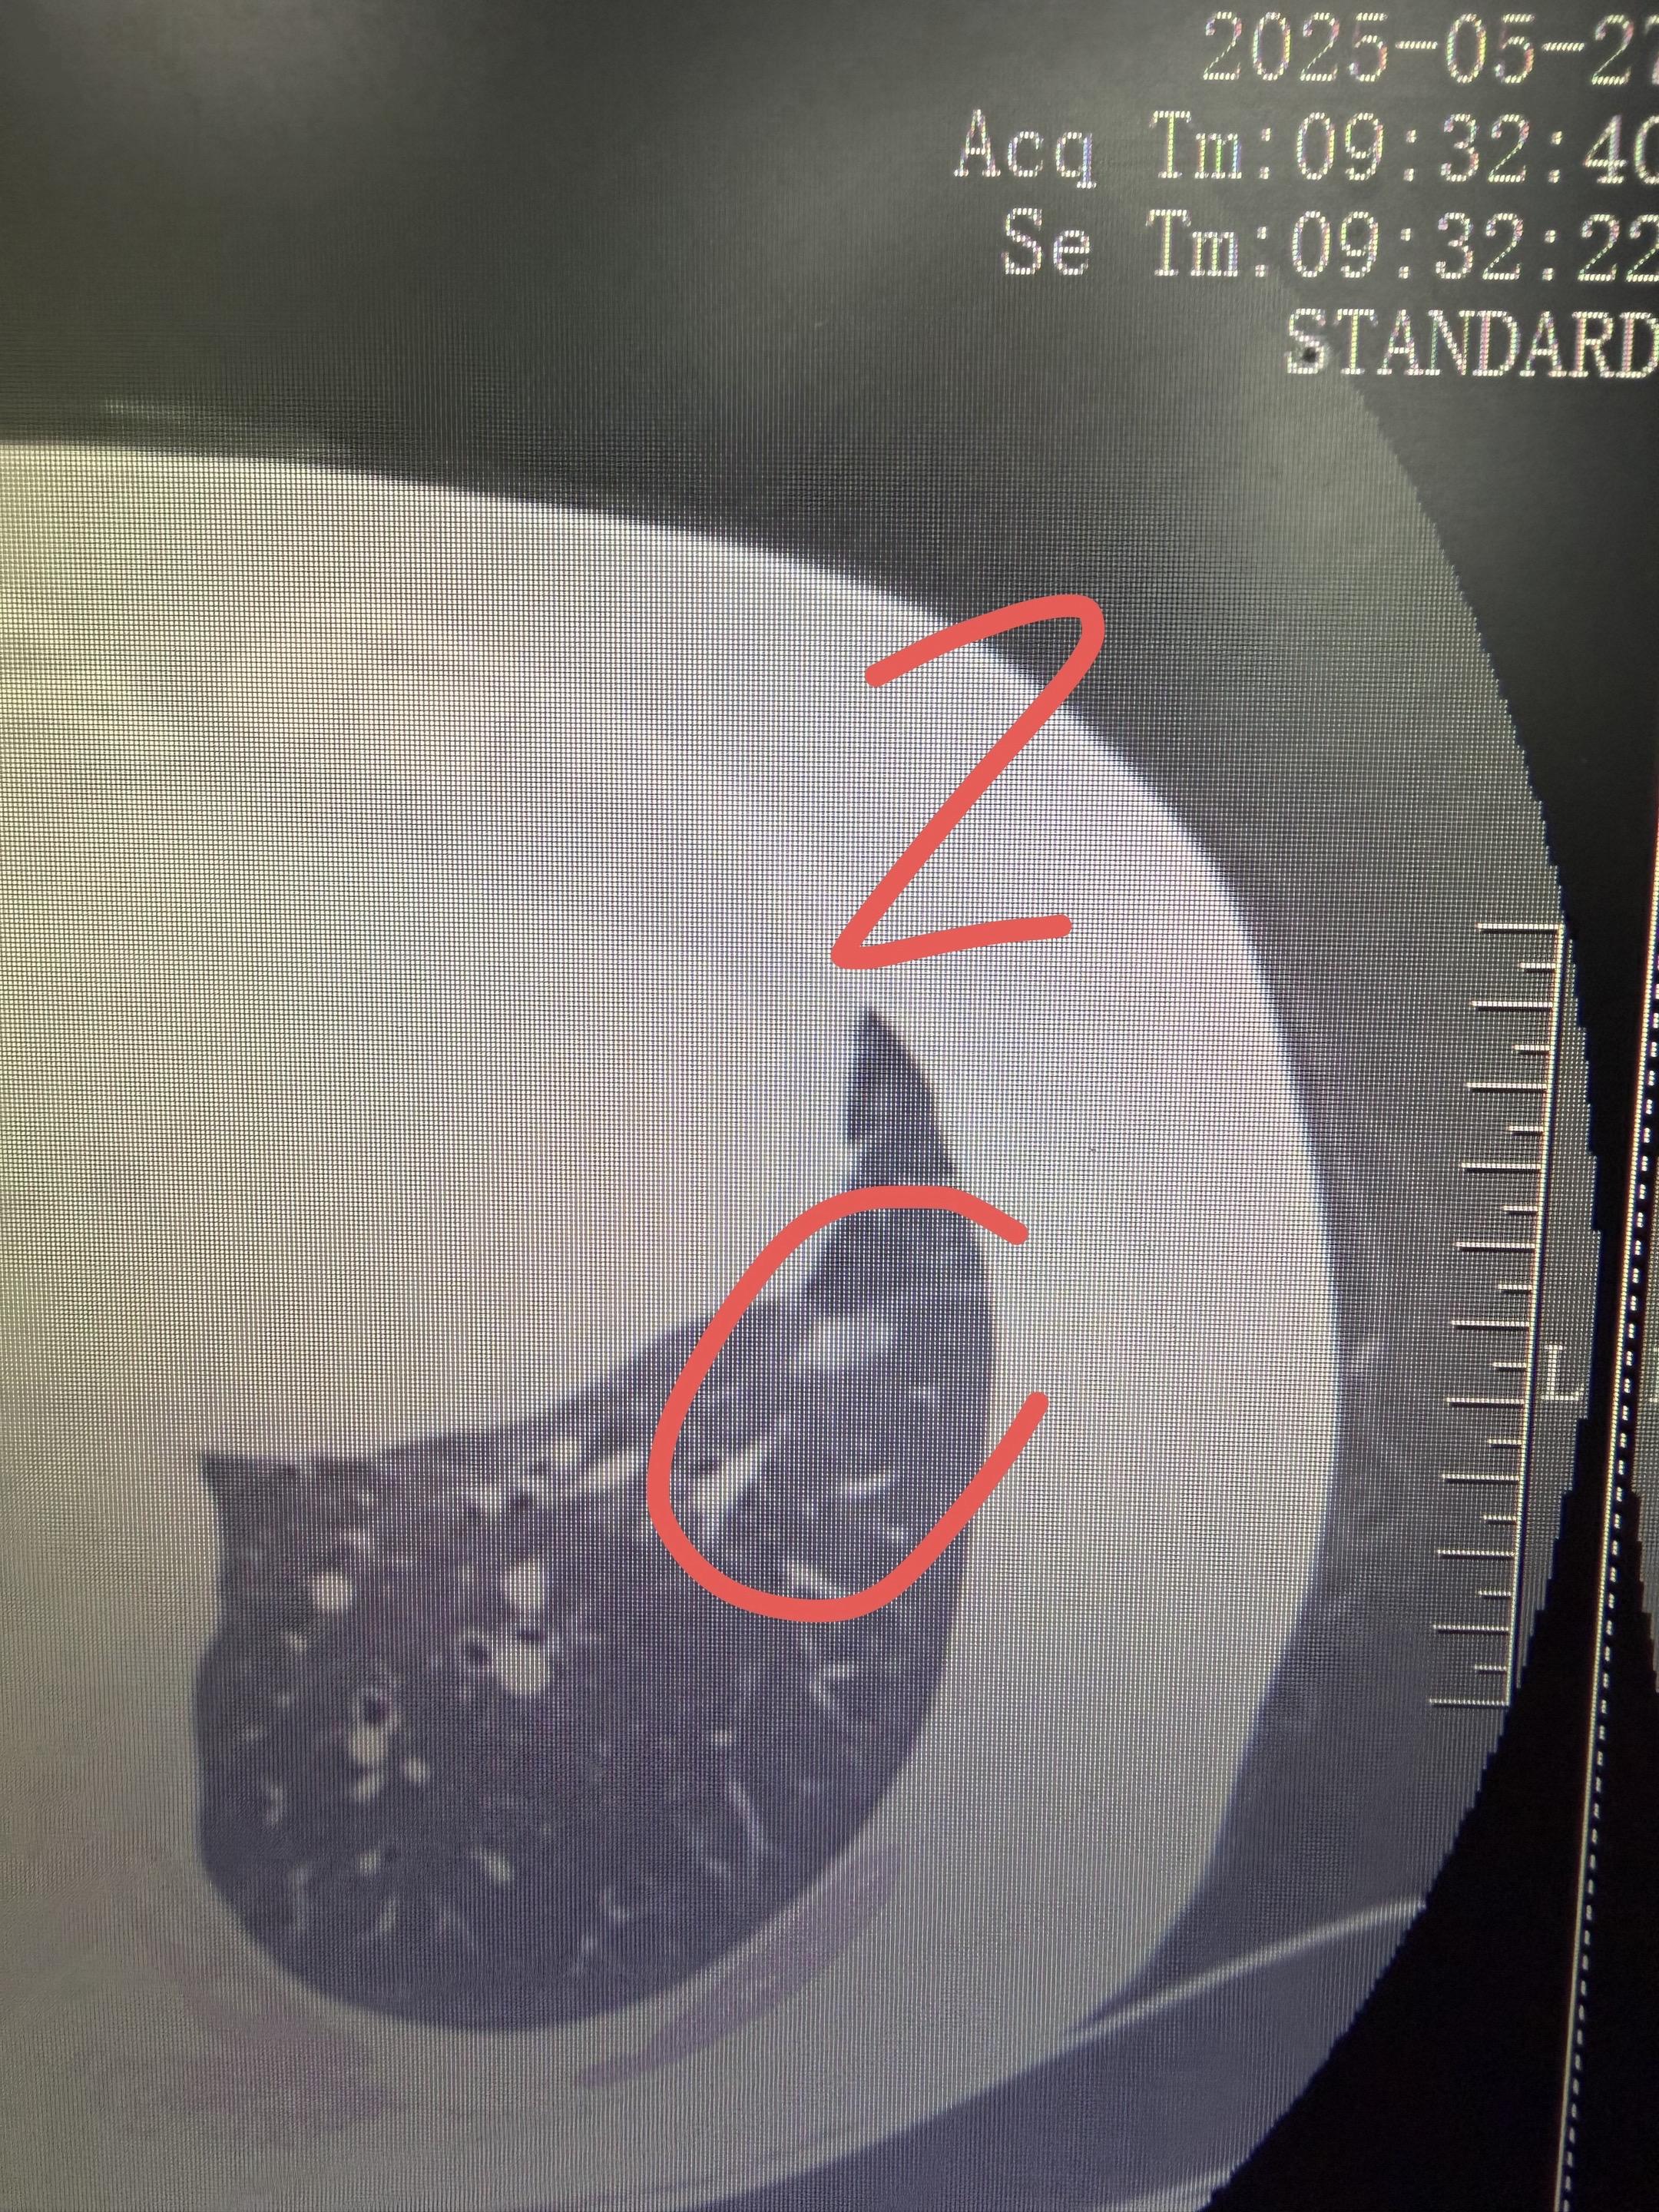

分享一个80岁多发结节的案例!如何治疗结。这个婆婆有4个有癌性磨玻璃结节,左侧两个1和2,右侧两个3和4。我们左侧做了腔镜楔形切除,术后病理浸润性腺癌,术后辅以治疗。右侧这两个结节在术后保守观察的过程中,明显缩小消失,应该是我们的术后辅助治疗起了作用。这就是,用一套治疗方案,解决了4个磨玻璃结节,该切的切,该保守的保守,病人损失最小化!